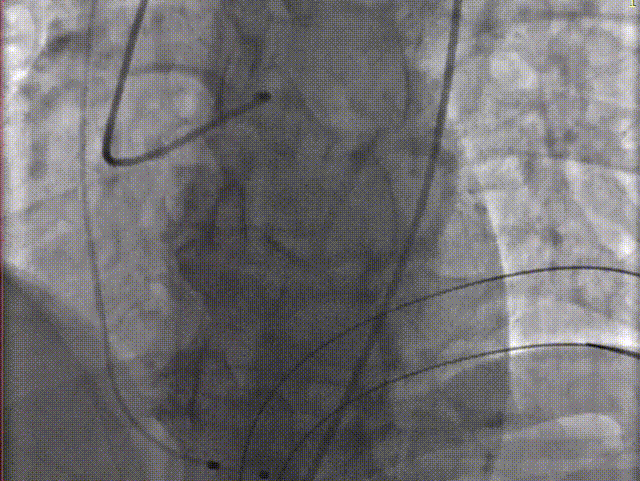

手术关键步骤

A.主动脉根部造影

B. 不前扩,输送系统一步到位

C. 应用交界贴合技术调整人工瓣膜,到安全梢固定位置,定位好,不需要回收,直接释放

D. 瓣膜释放后造影

E.球囊后扩

F. 最终造影